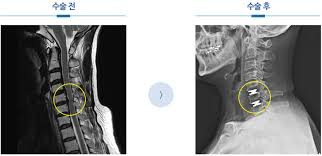

🚀 새 길의 핵심: 비절제·최소침습

① 뼈를 깎지 않는 이유

- 통증 원인의 상당수는 신경 압박·염증

- 구조 자체를 망가뜨리지 않고도 압박만 해소 가능

② 어떻게 가능해졌나?

- 고해상도 내시경

- 정밀 영상 유도 기술

- 미세 기구 발전

👉 정상 조직은 최대한 보존, 문제 부위만 정확히 치료